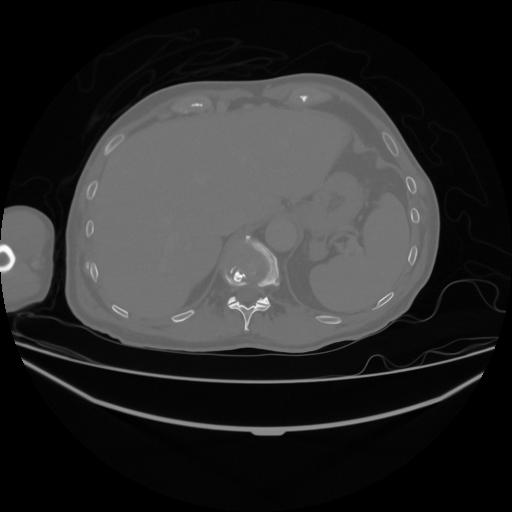

5 CUERPO,CE,Vol,1.0,CUERPO,,